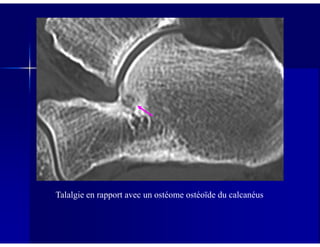

Talalgie en rapport avec un ostéome ostéoïde du calcanéus